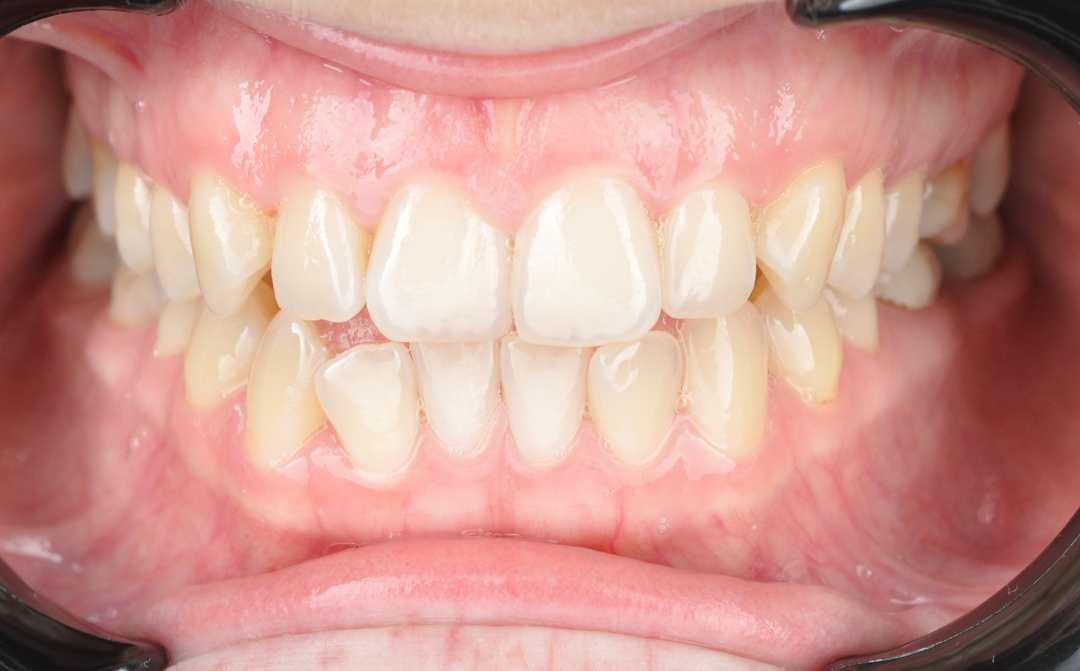

После

Результаты комплексного лечения

Комплексный подход команды «Архитектор Улыбок» дал закономерный результат, который был спрогнозирован еще

Здоровая улыбка

Ушел дискомфорт в суставе, исчезли боли в процессе жевания. Нижняя челюсть заняла стабильное, физиологичное положение.

Эстетика

Исправлен прямой прикус, восстановлена форма резцов, а улыбка стала не только красивой, но и здоровой с точки зрения биомеханики.